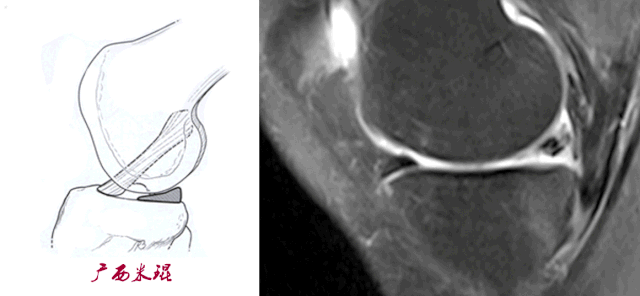

3)方向异常(ACL 下垂征):

-

有较完整的韧带低信号,但方向异常,呈下垂状。

一般见于股骨附着部的陈旧损伤,损伤的ACL下垂并粘附在PCL上。